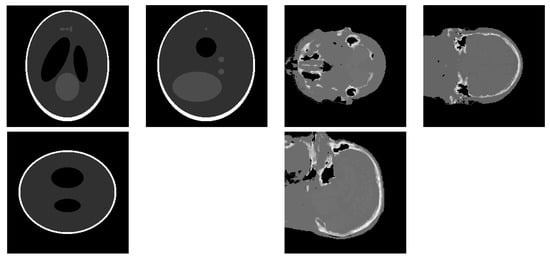

2. The Semi-Supervised Hierarchical Model

3.2. Simulation Results with a Limited Number of Projections

3.3. Simulation Results with a Limited Angle of Projections

3.4. Simulation with a Different Forward Model